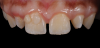

The rubber dam was removed from the mouth, and the excess material was removed with a No. 12B scalpel blade and a fine diamond bur. Next, the light-reflecting and light-deflecting zones were verified with a pencil and adjusted with finishing burs.11 The occlusion was then verified statically and dynamically using articulating paper and adjusted as needed. After finishing, the immediate postoperative polishing process was accomplished with a series of polishing discs followed by the use of a buffing disc with a diamond polishing paste (Figure 30). Eight days later, the patient returned to the office, and the final polishing was accomplished with polishing discs and diamond polishing paste (Figure 31 through Figure 35).

An assessment of the shape and shade of the final restorations was performed. It was noted that the incisal edges of the restored lateral incisors were not as white as those of the central incisors. Rather than adding additional stain to the lateral incisors, the patient expressed her desire to have some of the white staining removed from the central incisors using a resin infiltration technique after her orthodontic treatment. The final orthodontic treatment for the maxillary arch would involve closing the spaces in the anterior area, protracting the posterior teeth, and finishing in a Class II relationship. For the mandibular arch, the goal would only be to maintain the current positions of the teeth.